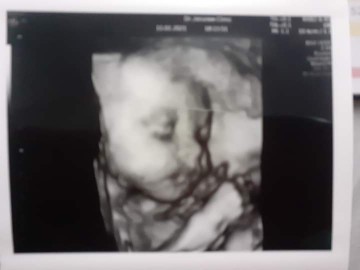

31+5แล้วค่ะ ลูกสาวค่ะ

ผู้หญิงจร้า คลอด 4 ธันวา 👧

ผู้หญิงค่ะ กำหนด15มีนา🥰